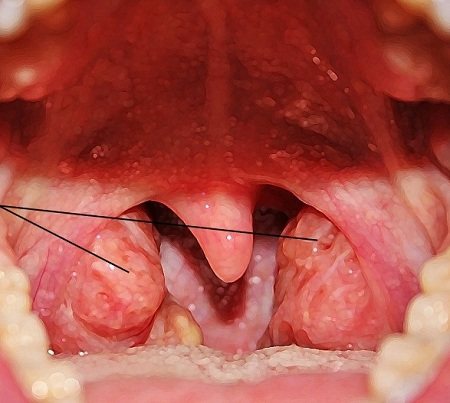

Увеличенные аденоиды

Гипертрофия аденоидов